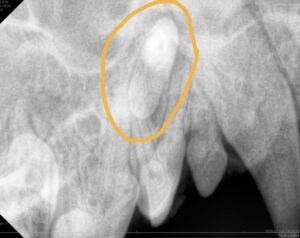

こんにちは! 世田谷区等々力にあります、けいこくの森動物病院です🌳 今回は当院で歯科処置を行ったわんちゃんの症例を紹介をします。 欠けた歯をレジンで修復 歯科検診で来院された6

5歳でも早くない!スケーリング症例